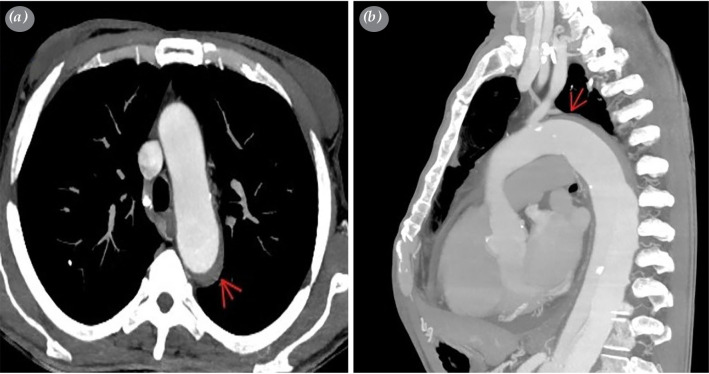

由于与开放手术相关的高死亡率和发病率,对于复杂的急性B型主动脉夹层患者,通常首选血管内治疗方法。逆行主动脉夹层是一种罕见的血管内手术并发症。在此,我们报道了一名53岁男性患者的手术治疗逆行主动脉夹层,该患者两年前有肝移植史并服用免疫抑制药物。

Endovascular treatment methods are often preferred in suitable patients with complicated acute type B aortic dissection due to the high mortality and morbidity associated with the open surgical procedure. Retrograde aortic dissection is a rare complication of endovascular procedures. Herein, we reported surgical treatment of a retrograde aortic dissection that developed after thoracic endovascular aortic repair in a 53-year-old male patient with a history of liver transplantation two years ago and taking immunosuppressive medication.